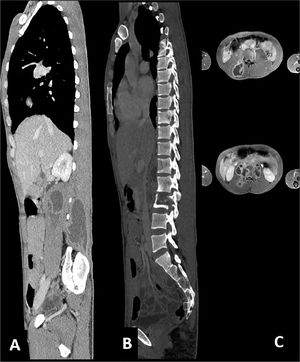

For these reasons, we decided to investigate that tumefaction with Computer Tomography (CT) scan and Nuclear Magnetic Resonance which showed liquefactive necrosis of Th10-Th11 and L2 (Fig. 1), and a large subcutaneous abscess. Several blood tests were performed, including a positive interferon-gamma release assays test, and HIV, HCV, HBV screening that turned out negative. He had an elevated C reactive protein (18 mg/dL), and a normal white blood cell count.

The patient was then admitted to the Infectious Diseases Unit and started treatment with MEM 2g three Times a Day (TID), amoxicillin/clavulanic acid 2.2g TID, LZD 600 mg two times a day intravenously (BID), and levofloxacin intravenously 500 mg BID. After one month of treatment, a CT scan showed a slight improvement of the abscess, but the bone injuries were unvaried (Fig. 2). We performed a second abscess sample showed a different resistance profile, now also showing resistance to meropenem. After approval by the hospital off-label drug committee, treatment with bedaquiline 400 mg daily for two weeks, followed by 200 mg three times per week, for 22 weeks, associated LZD 600 mg daily orally, RFB 450 mg daily, and amikacin 750 mg daily was started. Amikacin was discontinued after eight weeks. During treatment, a weekly Electrocardiogram (EKG) was performed. No QT prolongation was shown, but after 12 weeks of treatment, inverted T waves appeared; for this reason, several cardiological consultations and cardiac Magnetic Resonance Imaging were performed, but no cardiac dysfunction was found.